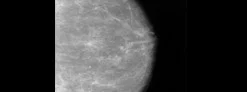

New Mammogram Advice and Correct Interpretation of Results

Mammogram Interpretation

Recent mammogram advice from the United States Preventive Services Task Force (USPSTF) has raised some eyebrows among women, especially given that the American Cancer Society has long recommended annual mammograms starting at age 40 for healthy women. The USPSTF’s updated guidelines, however, suggest a different approach based on their in-depth research and computer simulations. Here’s … Read more